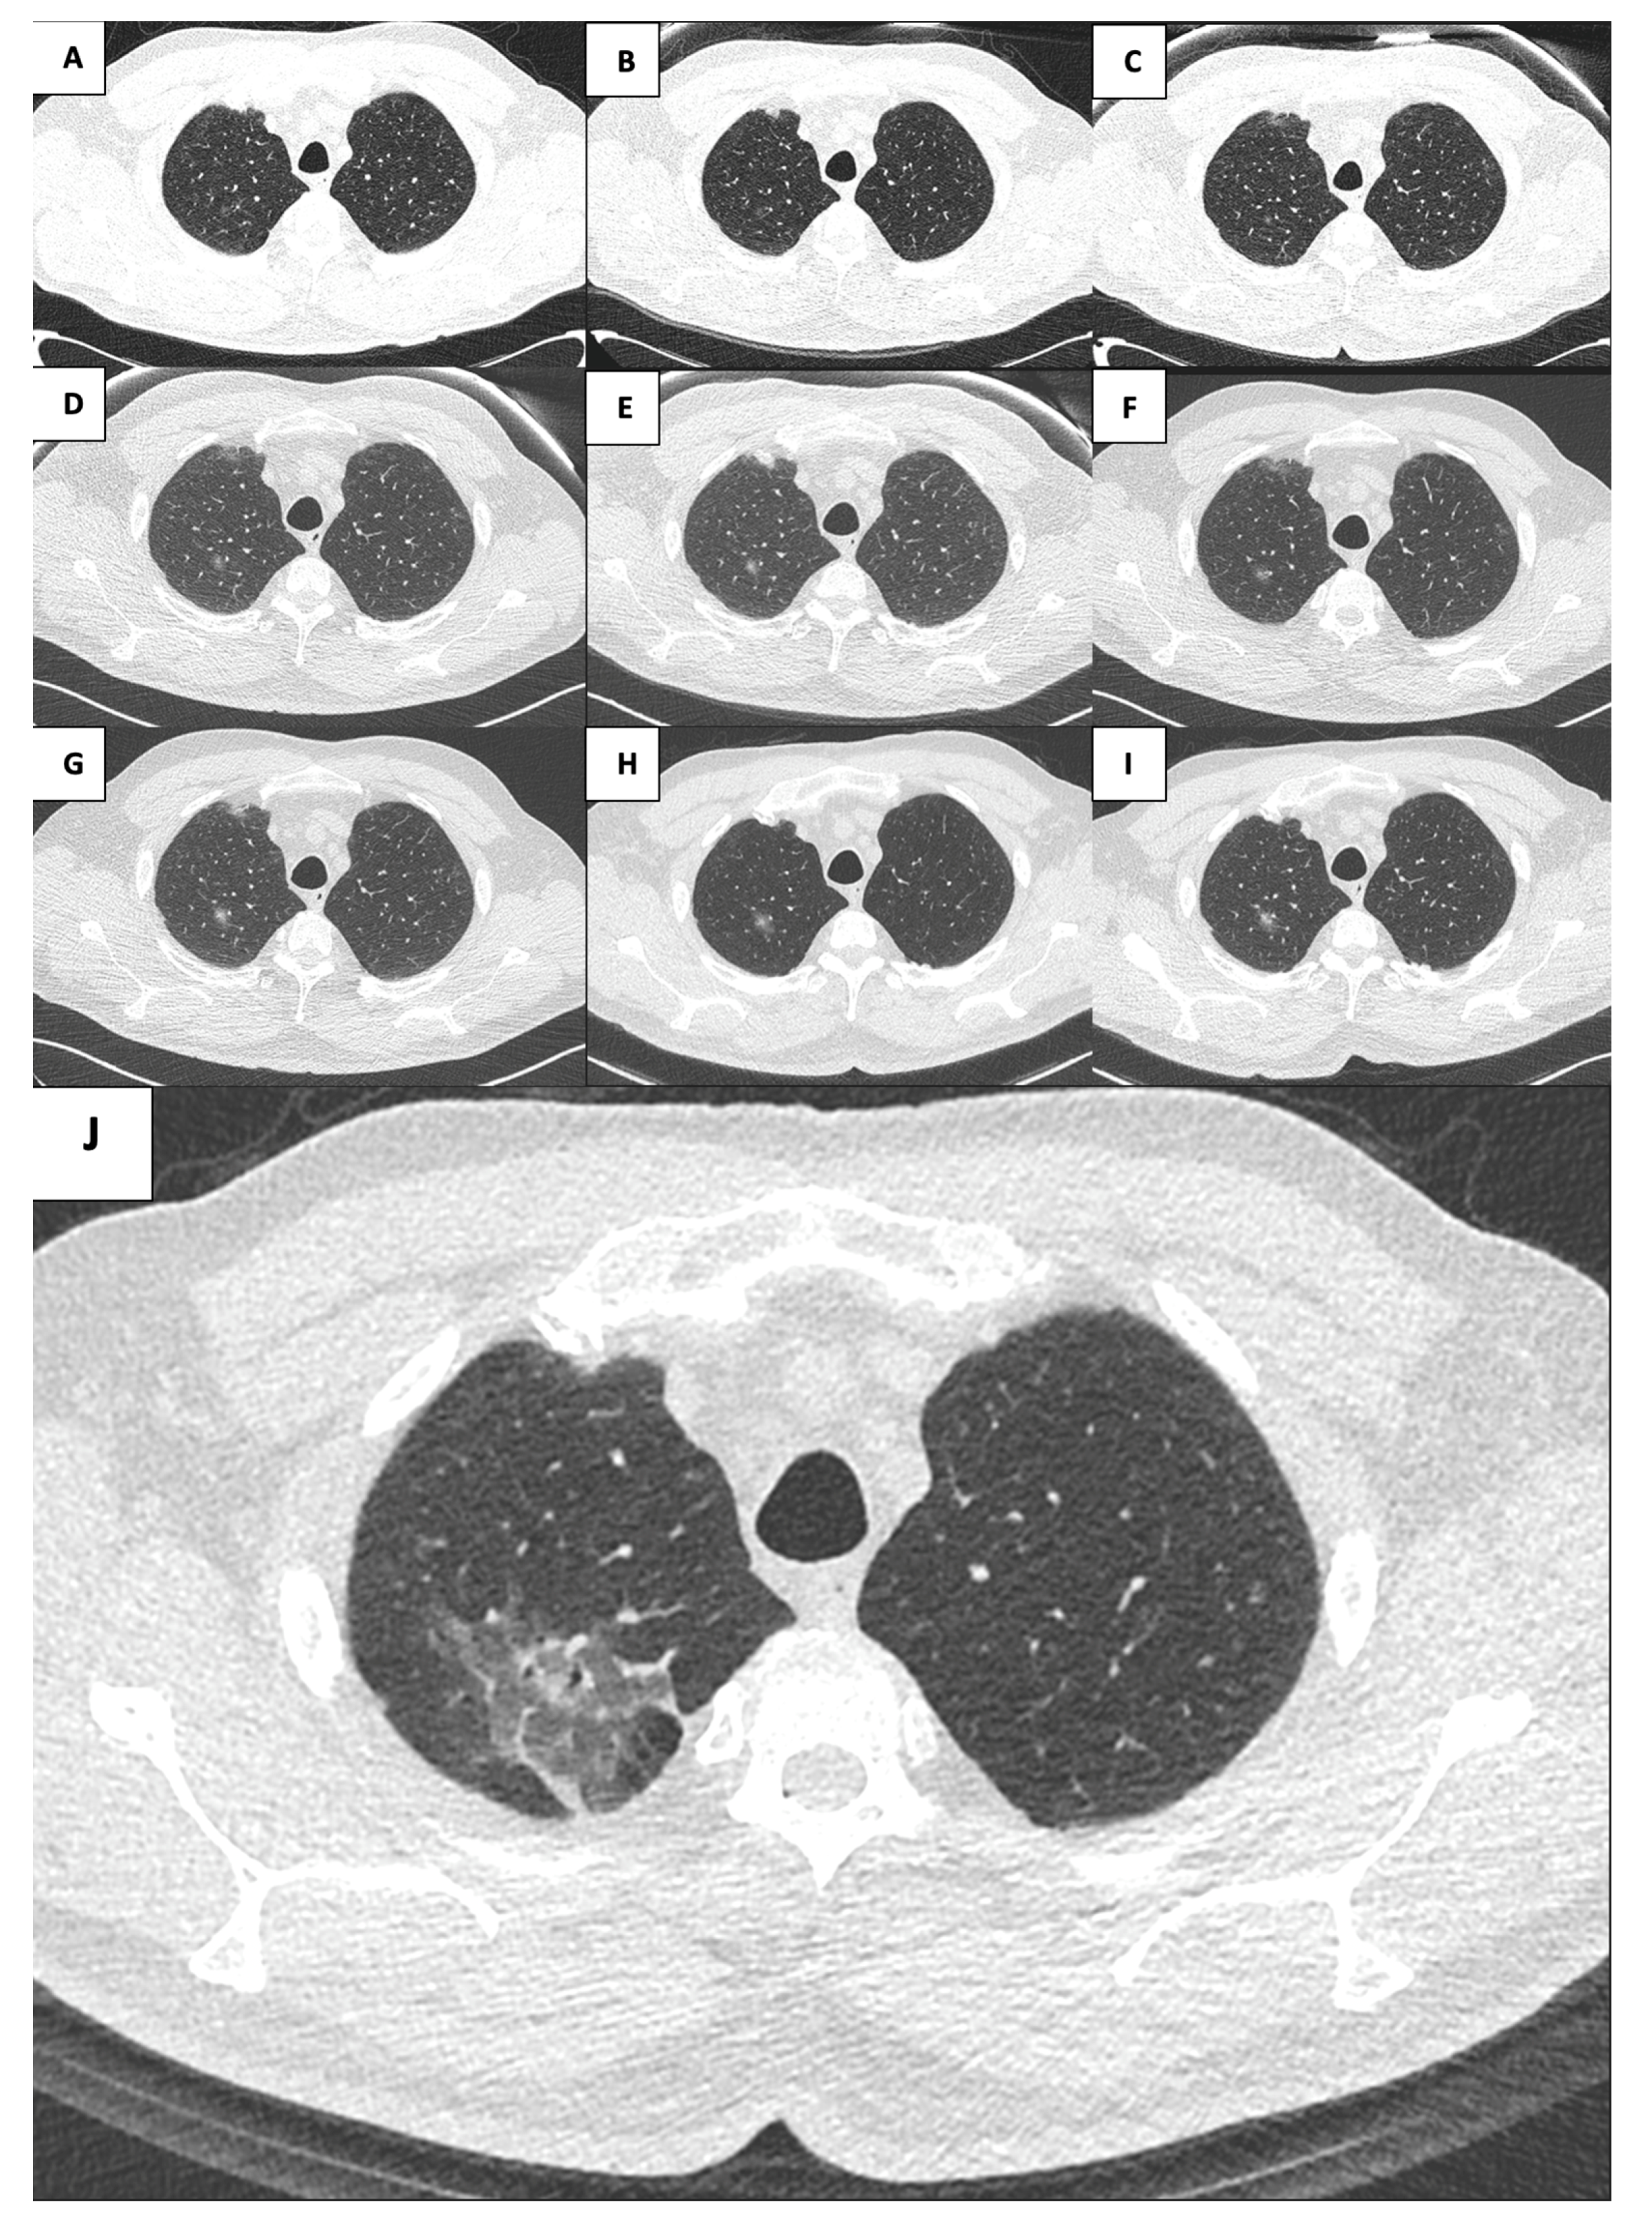

| Year | Dimension mm | Density HU | Solid Component mm3 |

|---|---|---|---|

| 2015 | 13.60 × 8.70 | −158 | 0 |

| 2016 | 11.50 × 9.00 | −292 | 0 |

| 2017 | 11.10 × 7.90 | −244 | 0 |

| 2018 | 15.00 × 8.50 | −190 | 47 |

| 2019 | 19.10 × 10.80 | −314 | 41 |

| 2020 | 16.90 × 10.30 | −208 | 145 |

| 2021 | 49.80 × 37.80 | −581 | 390 |